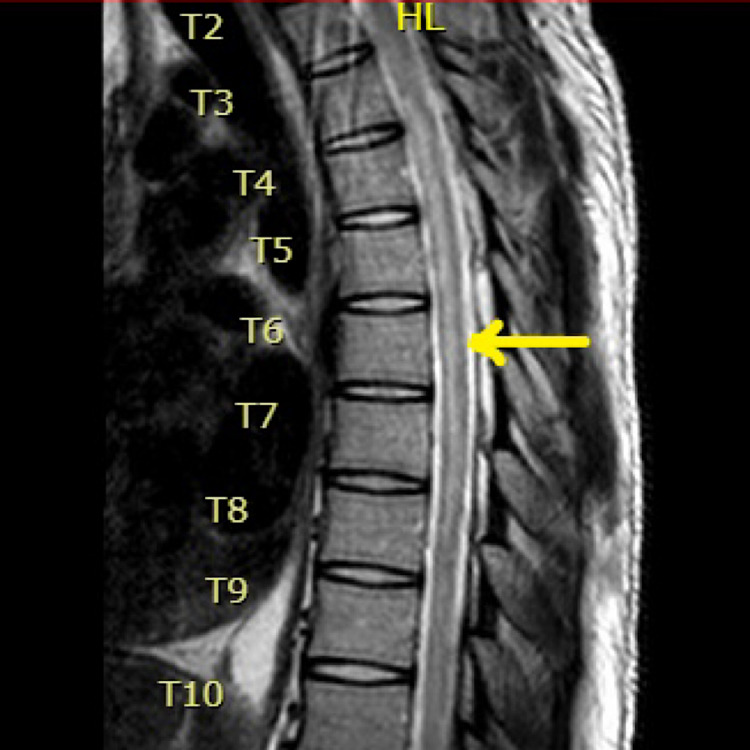

A 23-year-old male with a history of polysubstance abuse presented to the hospital with altered mental status (AMS) and hypoglycemia. He endorsed the use of alcohol, cocaine, and marijuana that day. It was confirmed with a positive toxicology screen. During this hospital admission, his physical examination was notable for paraplegia with no motor abilities from the T6 dermatome and below. Sensation was intact throughout all dermatomes but he was found to have urinary retention, which required a Foley catheter placement. Workup included an abnormal MRI showing T2 signal spanning from T2-T8, raising a high suspicion of a probable acute ischemic SCI (Figures 1, 2). MRI brain was normal, with no changes of demyelination.